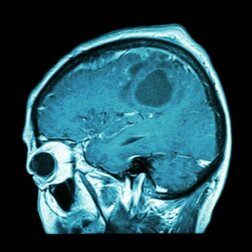

Gibt es bald einen Impfstoff gegen Hirntumore?

Impfstoff gegen Hirntumore

Die Forscher stellten jedoch fest, dass nicht alle Tumore genau gleich sind und auch nicht alle gut auf eine Immuntherapie ansprechen. Aus diesem Grund wurde an einer „Präzisionsimmuntherapie“ gearbeitet, um Patienten zu behandeln, die an einem Glioblastom leiden.

Das Glioblastom ist eine der Krebsarten mit der schlechtesten Prognose. Daher benötigten die Patienten, die zum Zeitpunkt der Studie darunter litten, einen personalisierten Impfstoff, um positive Ergebnisse zu erzielen. Aber wie machen die Experten das?